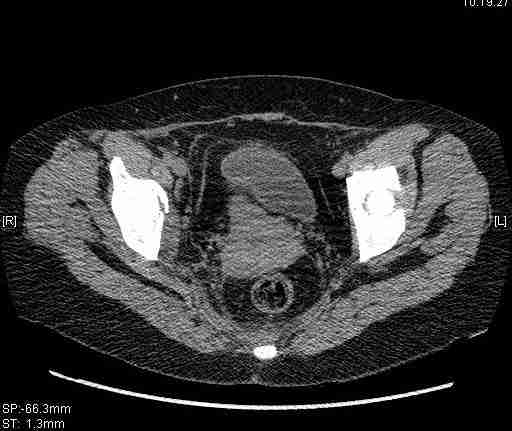

Re: Т-образный перелом вертлужной впадины

Удалось сегодня вывести пациентку в соседнюю больницу, где есть кт. Срезы сделаны только горизонтальные.